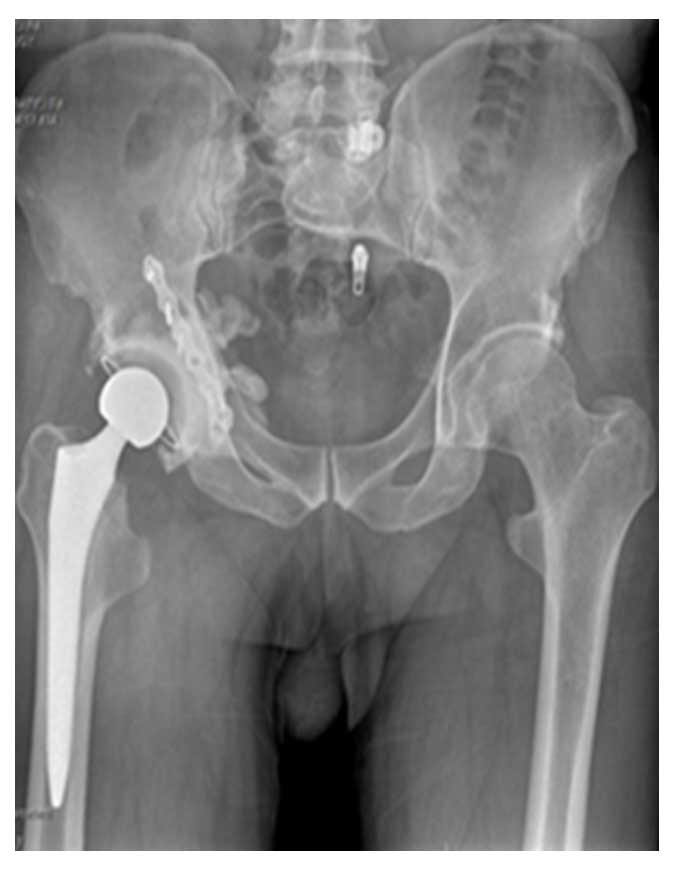

Ameliyat Sonrası: Röntgen ve tomografi kesitinde rezeksiyon sonrası uygulanan tümör protezi görülmekte.